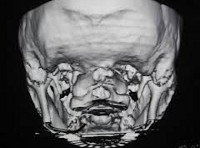

В ходе стандартного первичного обследования (ЭЭГ, Эхо-ЭГ и РЭГ) у пациентов с ассимиляцией атланта обычно определяется лишь повышенное внутричерепное давление. В случаях, когда ассимиляция атланта сопровождается симптомами поражения продолговатого мозга, необходимо исключение другой церебральной патологии: опухоли головного мозга, сирингомиелической кисты, абсцесса. С этой целью проводится КТ или МРТ головного мозга, которые в случае ассимиляции атланта могут выявлять признаки гидроцефалии. МРТ позвоночника позволяет судить о степени сдавления спинного мозга.